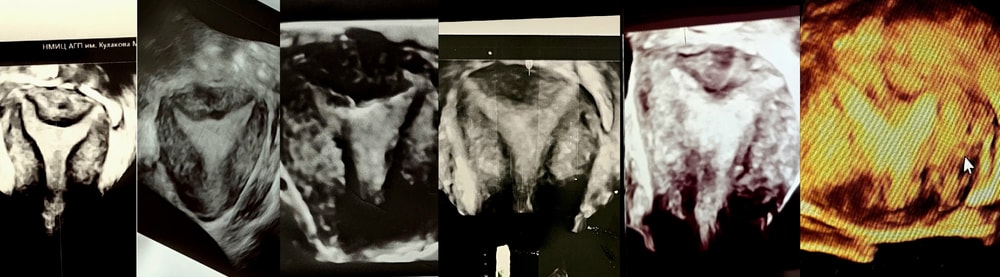

ГистероскопияРезультаты второй операции по удалению перегородки и синехий в Кулакова у Макияна. Приём у Каплиной. После операции в марте я пришла на плановое узи у Гуса.В июне 3д узи у Гуса, на котором он снова видит перегородку, и это после 2 операций в 2023 и в 2025. На мой вопрос, нормально ли это, он отвечает, что раз были операции, то всё соответствует норме. Это меня смутило. Ведь у большинства, кому делали операцию, уже после первой операции ничего не видят на узи. Также сказал про возрастное истощение яичников. Это меня расстроило. Хотя, смотрел он быстро и был явно не в духе. Сказал, что тонковат эндометрий. К Макияну я после этого узи не пошла, так как знала, что он скажет: "Всё хорошо. Это нормально". Так он и после первой операции говорил, а когда делал вторую, все же сказал, что да, там была еще перегородка и про т-образную матку. Месячные после операции стали скудные...можно сказать, что их почти и нет...Но я думала, что так восстанавливается эндометрий. В сентябре сдала гомоцистеин - оказался повышен. Остальные анализы в норме. После было ожидание приема гематолога Каплиной. К сожалению, даты приёма всё время переносились...И, если в декабре 2024 мне сказали, что ждать полгода, то в июне сказали, что ждать еще несколько месяцев. Я надеялась, что смогу попасть на прием в июне, как раз после операции бы прошло 3 месяца. Но, увы, пришлось ждать дальше. Так прошло ещё полгода... В ноябре амг сдавала перед узи, пришел 4,52. А вот АНФ пропал, с 1:1280 после беременности стал 1:160...Также перед ее приемом я делаю узи у Хегая в Кулакова, на котором он видит опять эту злополучную перегородку и синехии....но истощения яичников не видит, сказал, что всё нормально. Но предложил подумать о суррогатном материнстве...тк было уже много вмешательств...это меня расстроило. Через 2 дня состоялся приём Каплиной, на котором она говорит, что ей не нравится по узи моя перегородка и синехии. Надо снова удалять, а заодно и перегородку....хоть мне ее и удаляли 2 раза...Что эндометрий тонкий, возможно поврежден слой. И что после стольких вмешательств (7) однажды эндометрий перестанет расти.....По остальным анализам и анамнезу назначено лечение. Сказала, что надо было начинать планирование через 4 месяца после той операции, я сказала, что так и хотела, тк думала, что попаду к ней на приём в это время, а я ждала...Спросила её, что, опять идти в Кулакова? На что ответ был, что они лучше всех убирают эти перегородки. Да, кому-то, может и везёт. Почему же мне не могут за 2 раза убрать?? Опять идти к Макияну??? Я к нему не хочу...у меня ощущение, что это замкнутый круг...просто не знаю. Может, есть, кто сделает лучше и внимательно?Я была в отчаянии...после всего я была в каком-то ступоре.....я прорыдала тот день....и не хотелось ничего. Я понимаю, что могла, конечно, не ждать её приёма, и начинать самой планировать, пока не было синехий, вступить снова в чат Кати. Но, с другой, стороны, я хотела убедиться в точности назначений. Так как у Кати были другие дозировки. У Каплиной дозировки выше, плюс, добавили капельницы Иммунноглобулина. Сейчас я в какой-то прострации...Иногда думаю оставить эту затею. Сколько можно мучать организм этими операциями....И морально терять столько беременностей тяжело..правда уже подумать о суррогатном материнстве или усыновлении. С другой стороны, Каплина сказала, что я еще не пробовала выносить на полной терапии...и надежда есть. Тем более 11 лет идём к этому. Столько прошли. И потом буду жалеть, что когда-то был шанс...Девочки, помогите, пожалуйста. Мне важен совет. Кто делал несколько операций на перегородку? Оставалась ли у вас после всех операций всё равно перегородка? Были ли случаи вынашивания? Почему ее не убирают до конца? Может, хирург убирает только по определенному допуску? И боится перфорации или того, что в беременность может быть разрыв матки? Может тогда и не стоит трогать эту переписку? Тк Каплина сказала, что может они ее не доубрали, тк она кровить начинает, или неудобно расположена или состоит из каких-то тканей...Также вопрос по хирургам. Кому-то еще удаляли перегородку где-то кроме Кулакова? В Кулакова слышала, что Аракелян хорошг делает. Несколько моих знакомых делало. Уже родили в том году. Хорошо ли убрали? Знаете ли еще других хирургов в Москве или других городах? Или лучше метод офисной гистероскопии холодными ножницами? Чтобы было менее травматично...Или перепроверить узи?Буду благодарна вашим советам и ответам...а то уже не знаю, что делать и куда идти...Прикладываю коллаж моих 3д узи, начиная от до операции и после 2-х операций в конце. Посмотрите, у вас также, кому делали?